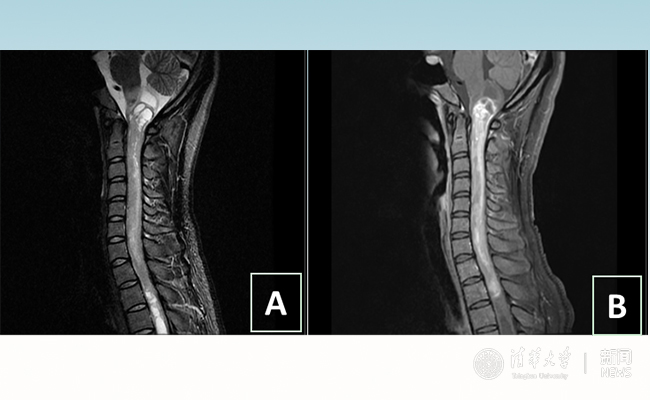

2018.01拯救“90后”女孩 清华长庚神经外科切除20多公分髓内肿瘤

“愿得韶华刹那,开得满树芳华。”27岁的患者小甜(化名)在清华大学附属北京清华长庚医院成功进行了手术,神经外科主任王贵怀为其切除了自延髓至胸髓的长达20余公分的脊髓内肿瘤。1月9日,小甜顺利出院,再续芳华!